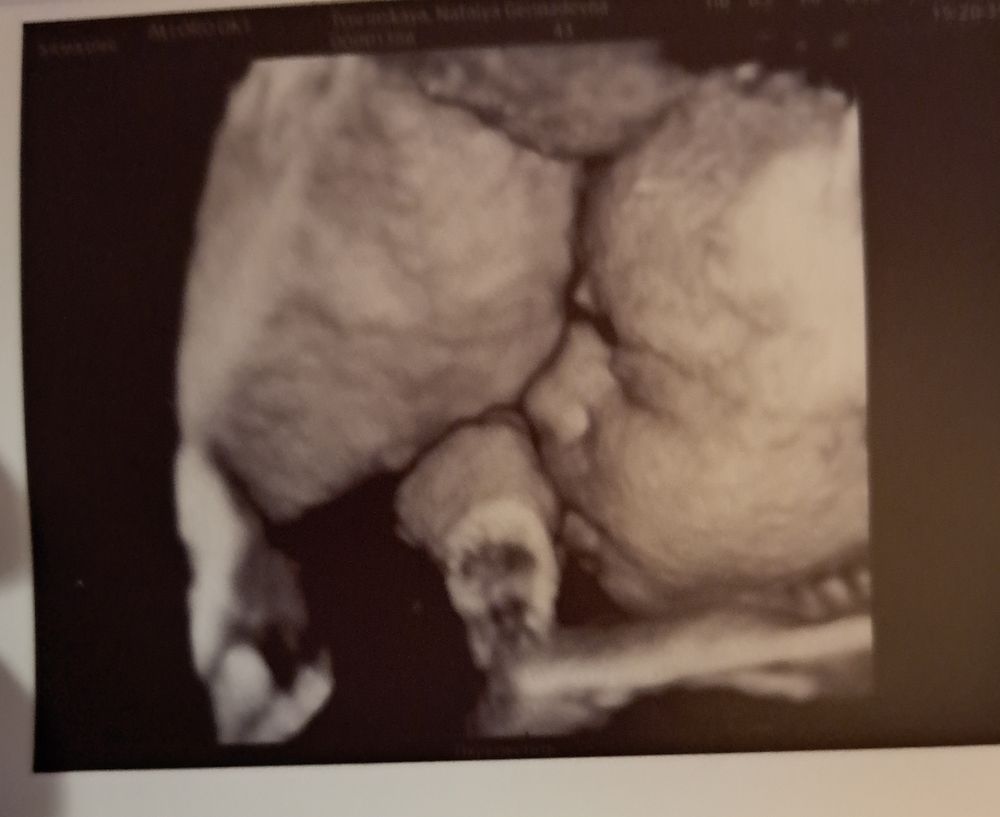

В 33 недели 3Д